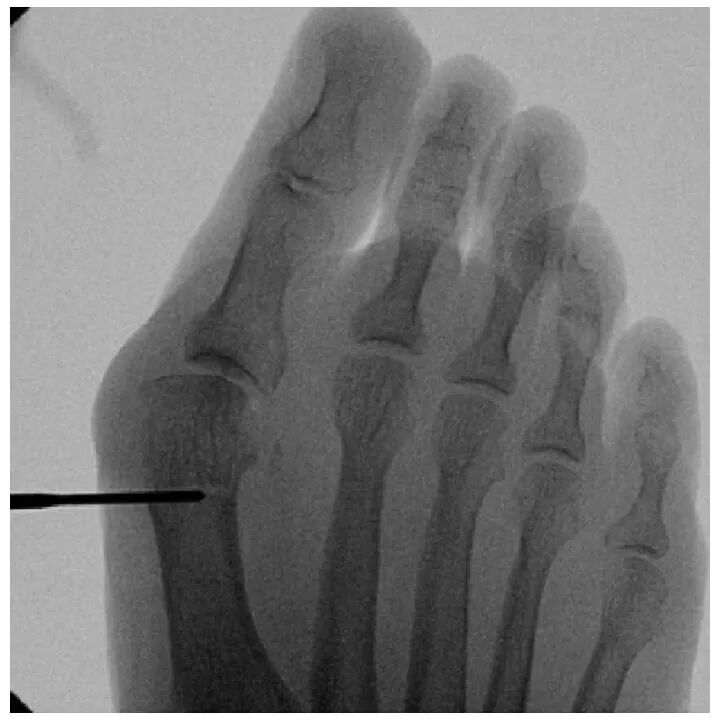

通过同一个内侧切口,引入2.0×19.5毫米钻头(进行第一跖骨截骨术。截骨术包括3个不同的截骨面:背侧、内侧和外侧。使用Sawbone模型来说明进行三平面截骨术所涉及的不同截骨及其方向。背侧截骨的深度为第一跖骨高度的1/3。内侧截骨从远端向近端开始,与跖骨长轴成45度角。再次通过内侧切口插入钻头进行外侧截骨,此时与跖骨长轴成30度角。内侧截骨比外侧截骨更短、更陡峭,以促进远端骨块的可控侧向平移。这种几何设计倾向于将位移限制在单一方向,提高矫正的可预测性。为避免头部抬高,钻头在冠状面朝向约10度的跖侧方向。

截骨完成后,将弯曲的骨膜剥离器插入截骨部位,以平移第一跖骨头。通过近节趾骨基部内侧的3毫米切口进行额外的Akin截骨术。使用一枚2毫米克氏针通过截骨端沿拇趾内侧软组织向远端穿过,从趾尖的跖内侧穿出。然后将克氏针逆行插入第一跖骨的髓管。